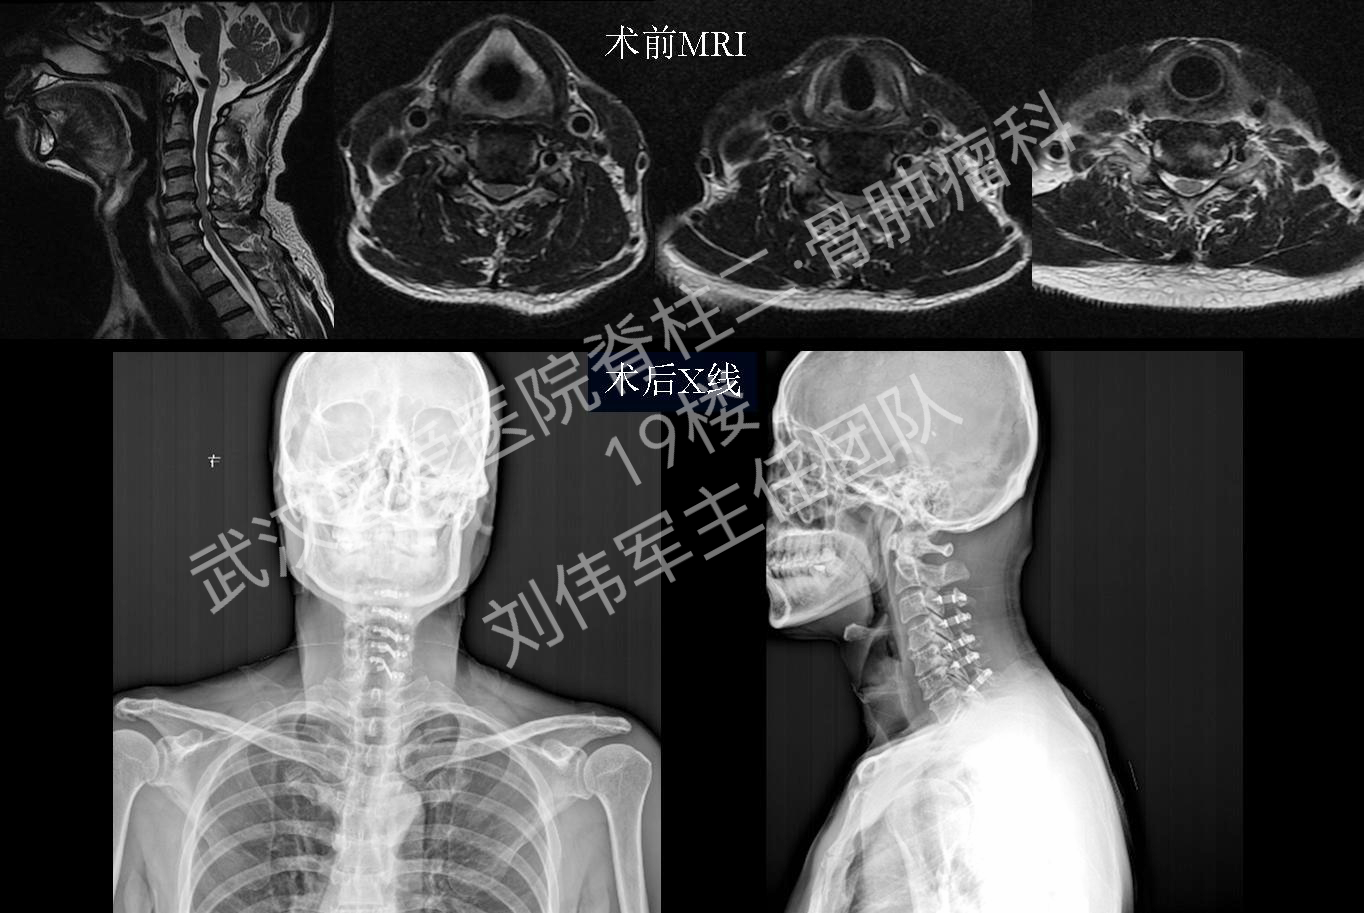

2016年刘主任团队典型病例:脊髓型颈椎病-后路

1364x913 - 831KB - PNG